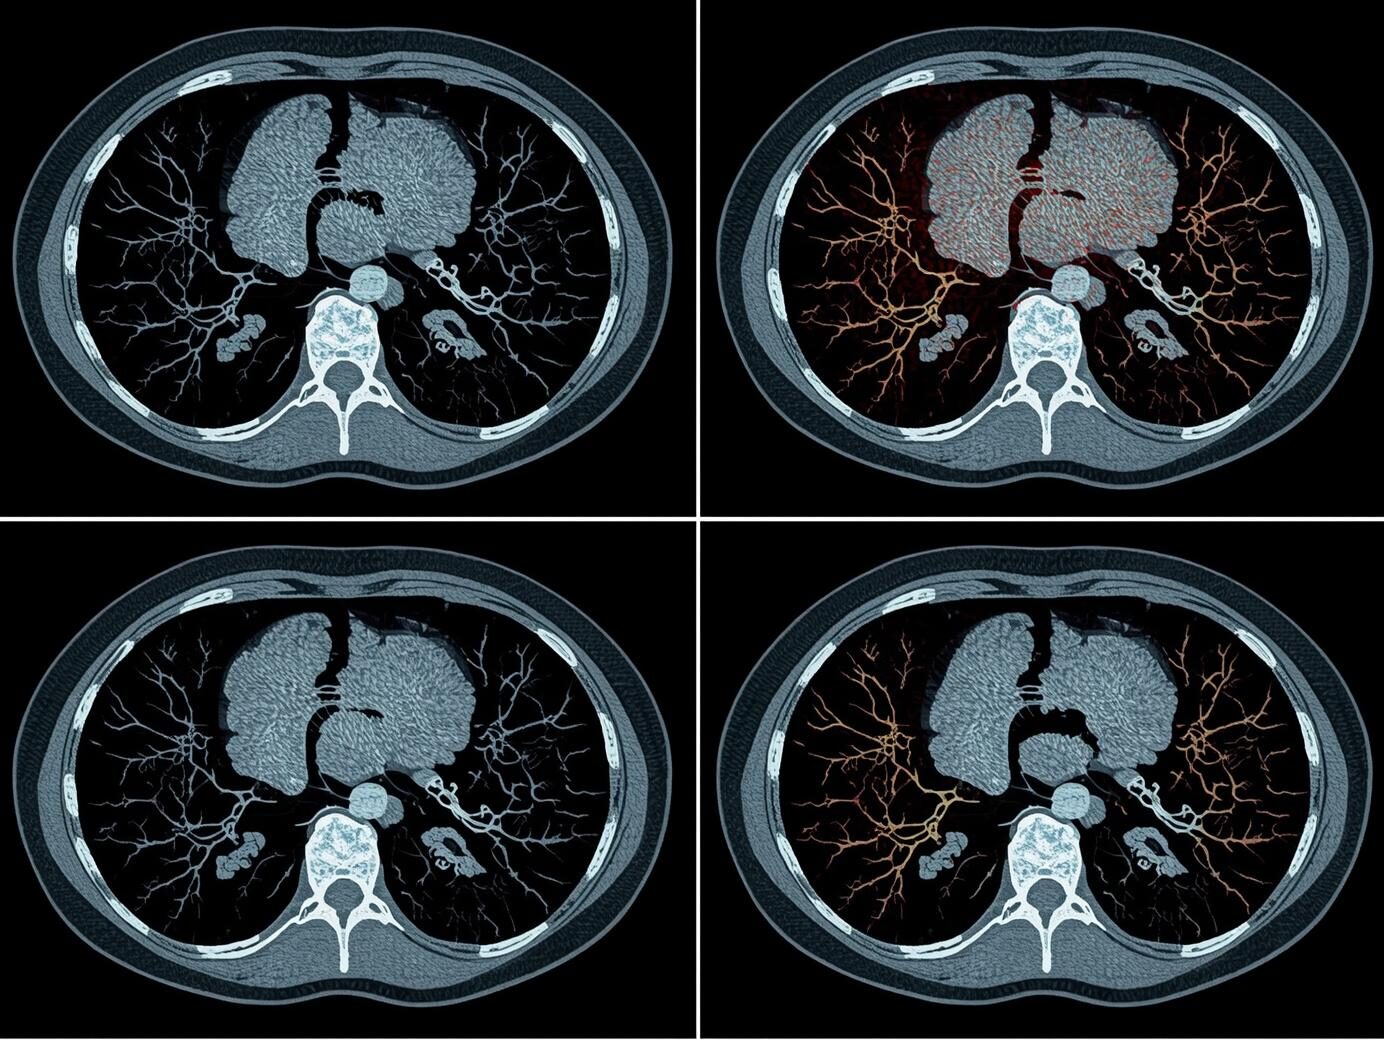

La IA nos permite ver “más allá de lo evidente”, detectar patrones ocultos en la salud y revelar diagnósticos invisibles al ojo humano.

No se trata de que la IA vaya a reemplazar a los médicos o a enfrentarse con ellos. Ahora es la IA con los médicos. Es una invitación a que los profesionales de la salud se capaciten y trabajen junto a herramientas de inteligencia artificial para el diagnóstico, que pueden ayudarlos a identificar patrones imperceptibles al ojo humano.

Estoy seguro de que, en un futuro cercano, la IA se convertirá en un sistema capaz de detectar correlaciones complejas en grandes volúmenes de datos médicos, revelando respuestas que antes eran invisibles para los doctores, y estableciendo patrones con un “sexto sentido” casi tan refinado como el instinto humano.